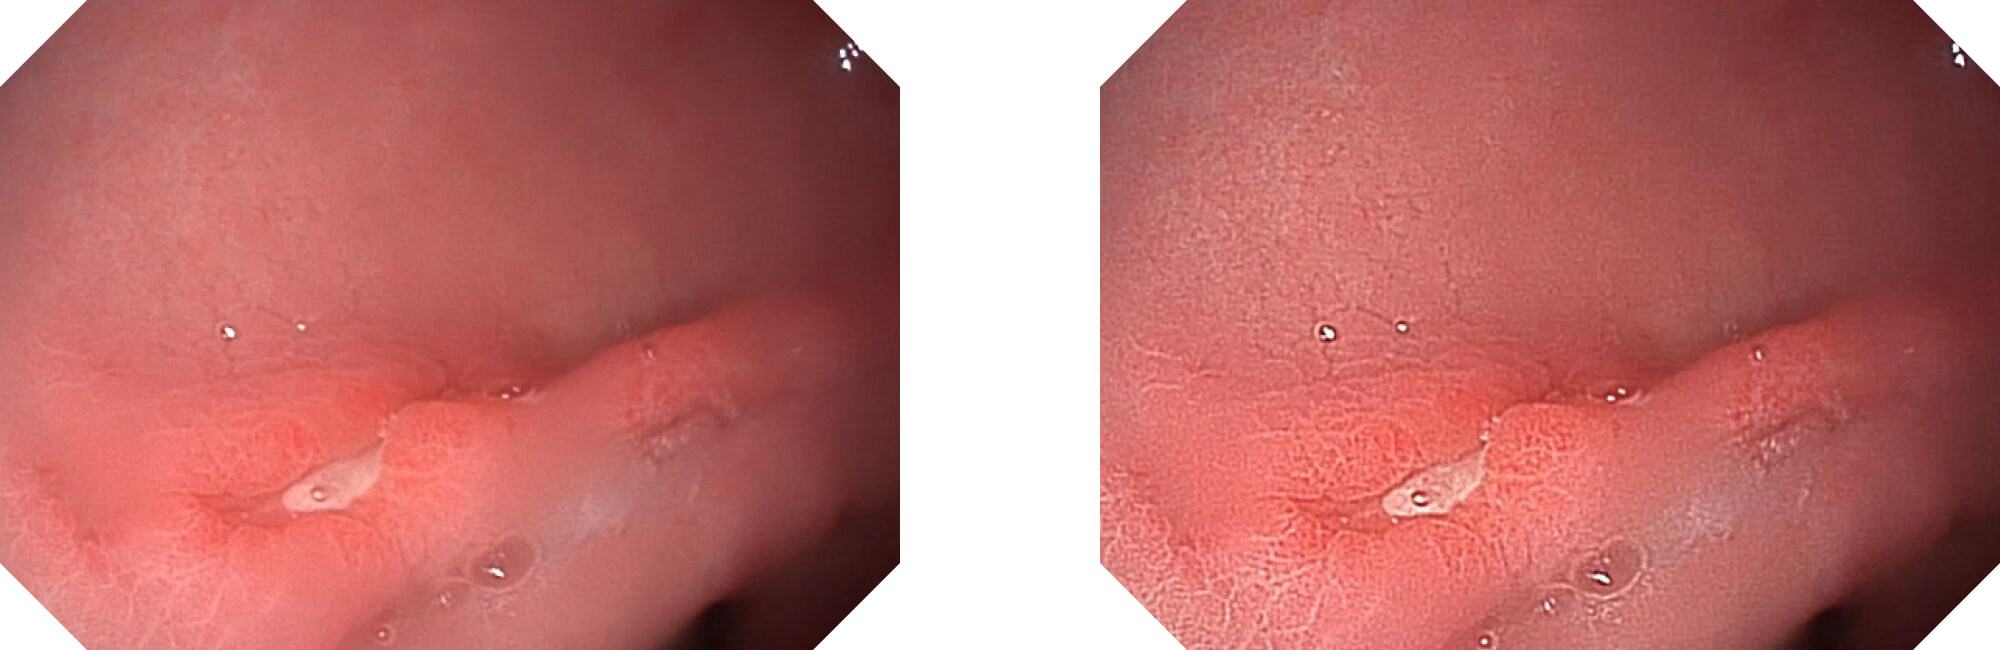

高清数字信号结合构造强调和色彩增强,多重图像处理技术能让每一个图像都清晰可见。

• 构造强调

• 色彩增强

• 电子放大